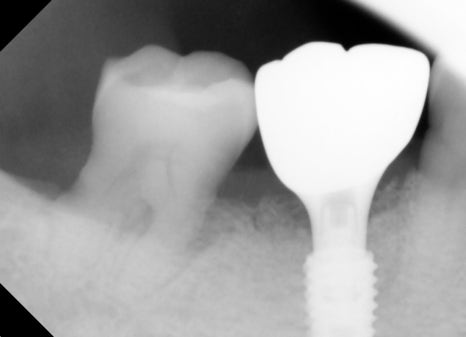

The Implant Placement Process

After molar extraction, implant placement is performed.

At this stage, what matters most is the condition of the bone.

Because the molar area often lacks sufficient bone, bone grafting is often performed together.

In this patient’s case as well,

guided bone regeneration and allogeneic bone grafting were performed together.

Implant price varies depending on whether such bone grafting is needed.

At an implant dental clinic, it is important to secure initial stability

so that the implant can be fixed firmly.

Prosthetic Treatment and the Final Steps

The final stage of implant treatment is the prosthesis.

The prosthesis is

The part that functions as the actual tooth,

and it is made to match the patient’s bite and shape.

In this case,

a custom abutment and a zirconia crown were used.

Molar implants are under strong chewing force in particular,

so bite adjustment is very important.

At the implant dental clinic, stability is ensured by checking the bite multiple times. Implant price can also vary depending on

the precision of the prosthesis.